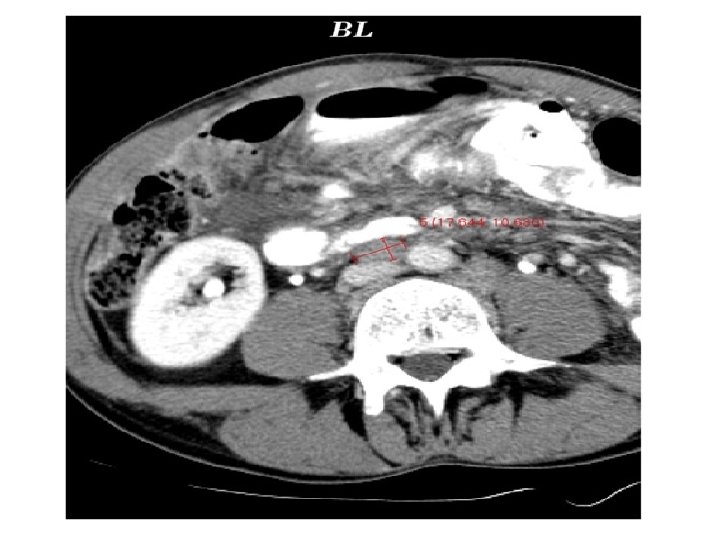

Takipte hedef lezyon ölçümü: Bazale göre farklı yön ve kesit olsada en geniş yerinden ölçün!!! Takip Bazal